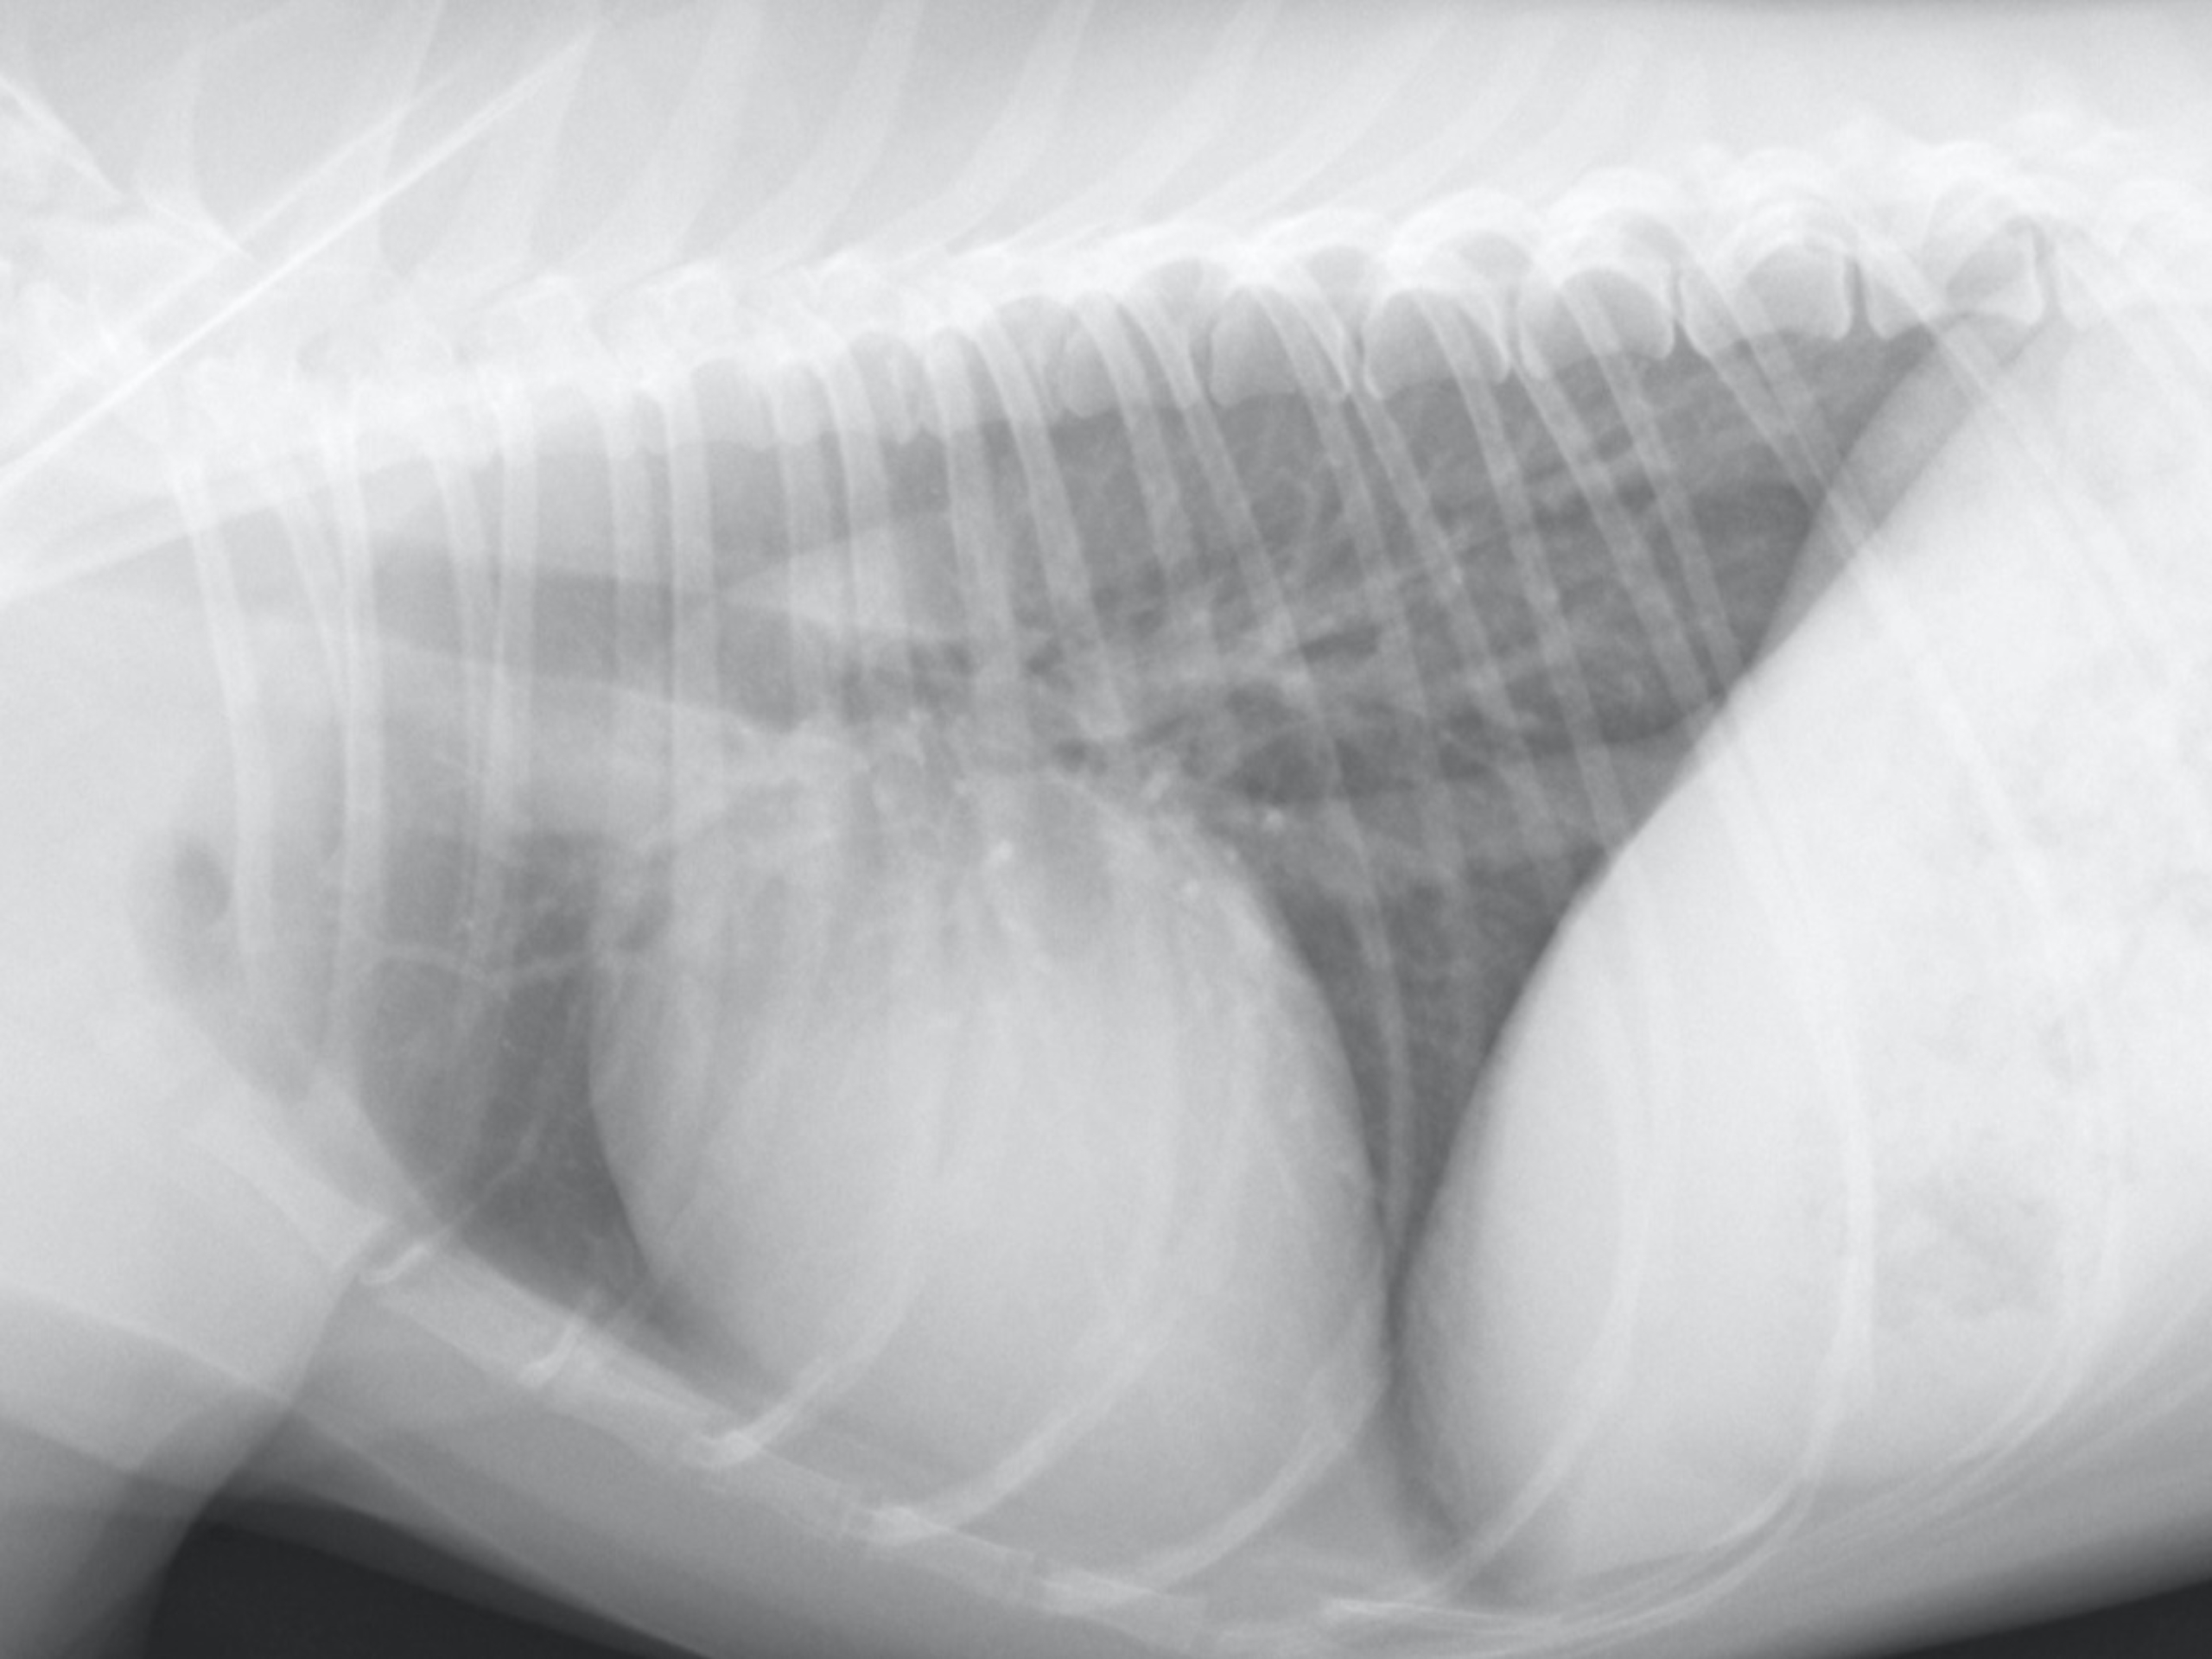

真ん中の丸い陰影が心臓で正常心です。

弁膜症によって心拡大しています。図3へ

徐々に進行して逆流が増えるとその分血液を多く前方(体)に送る必要ががるので、心臓が大きくなります。これは心臓が病気に対応している状態と言えます。この時期の後期になると疲れやすい症状が出ることもありますが、犬ではほとんどの場合は症状は分かりません。悪化してくると興奮や運動で発作的に失神(意識がなくなる状態)を起こすこともあります。この時期から拡大した心臓に押されて咳が出てくる子も多くなります。図3のように心臓が気管を上の方向に押し上げてしまっていることによるものです。